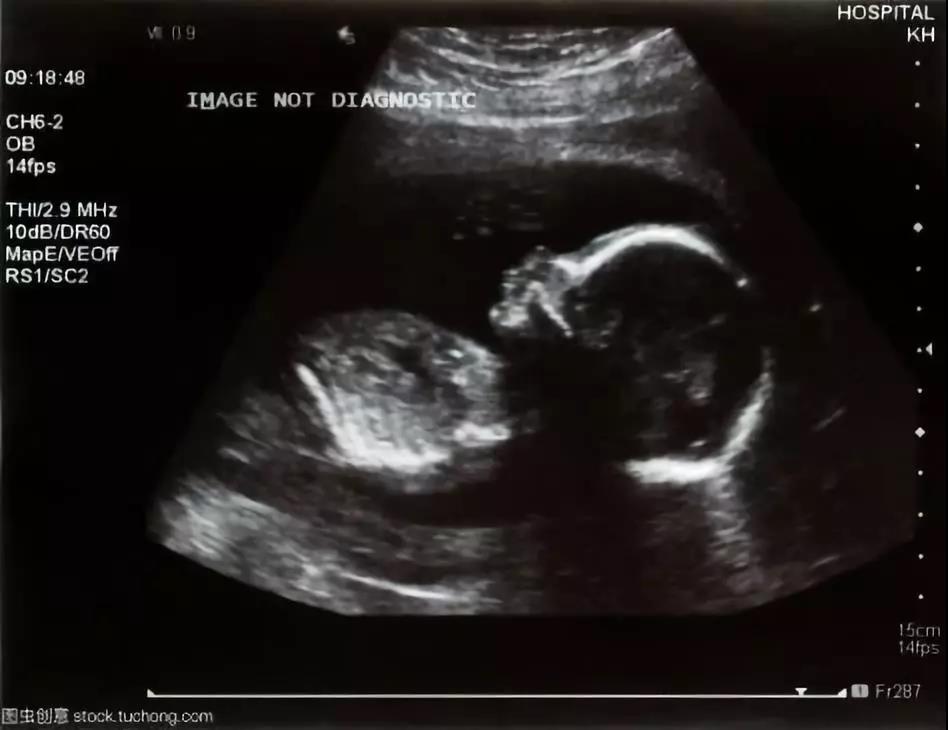

医院里最常见的是二维超声,包括黑白B超和彩超,它们的图像是身体里某一切面的平面图。彩超并不是彩色的,全称是彩色多普勒超声,是在黑白B超的基础上增添了血流信息,经过计算机处理不同血流信号会展示出不同颜色。彩超便于判断身体内器官和病变血流情况,利于一些病变的鉴别和诊断。